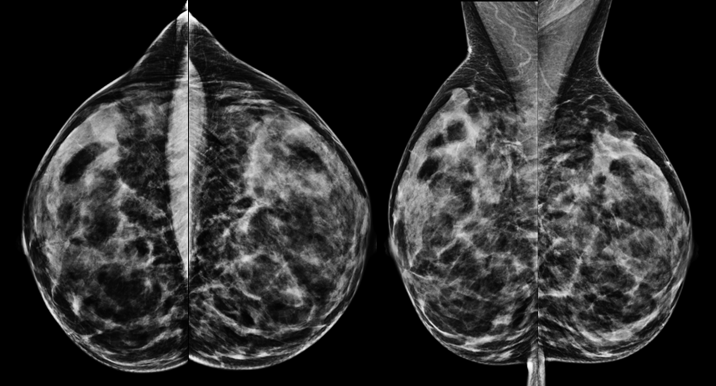

Mammographie einer 52jährigen Patientin zur Brustkrebsfrüherkennung